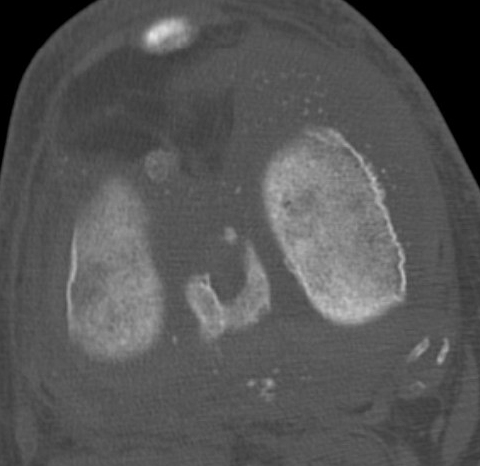

CT

Demonstrate osseous / calcified bodies